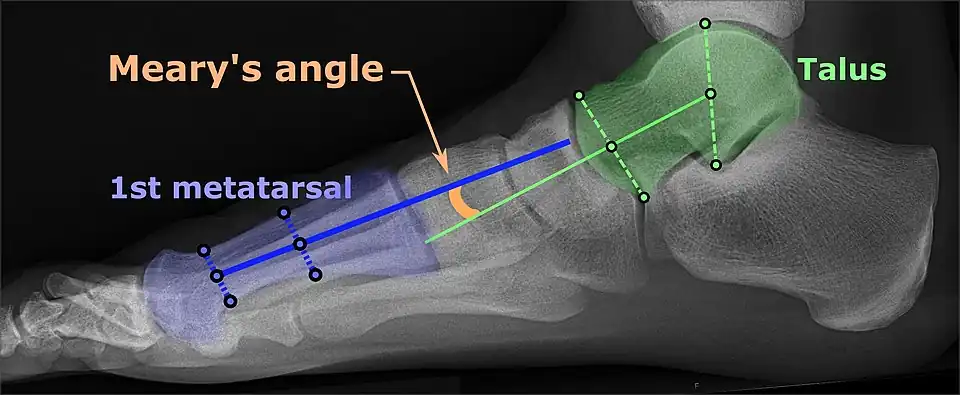

On weightbearing projectional radiography, pes cavus can be diagnosed and graded by several features, the most important being medial peritalar subluxation, increased calcaneal pitch (variable) and abnormal talar-1st metatarsal angle (Meary's angle).[17] Medial peritalar subluxation can be demonstrated by a medially rotated talonavicular coverage angle.[17]

Pes cavovarus, the most common type of pes cavus, is seen primarily in neuromuscular disorders such as Charcot-Marie-Tooth disease and, in cases of unknown aetiology, is conventionally termed 'idiopathic'.[20] Pes cavovarus presents with the calcaneus in varus, the first metatarsal plantarflexed, and a claw-toe deformity.[19] Radiological analysis of pes cavus in Charcot-Marie-Tooth disease shows the forefoot is typically plantarflexed in relation to the rearfoot.[2]